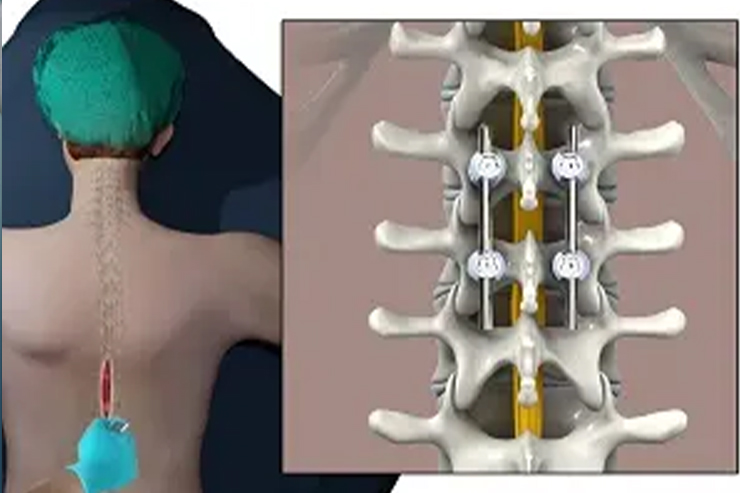

Spinal fixation or fusion stabilizes the spine, reduces pain, and corrects deformities caused by injury, degeneration, or spinal instability....